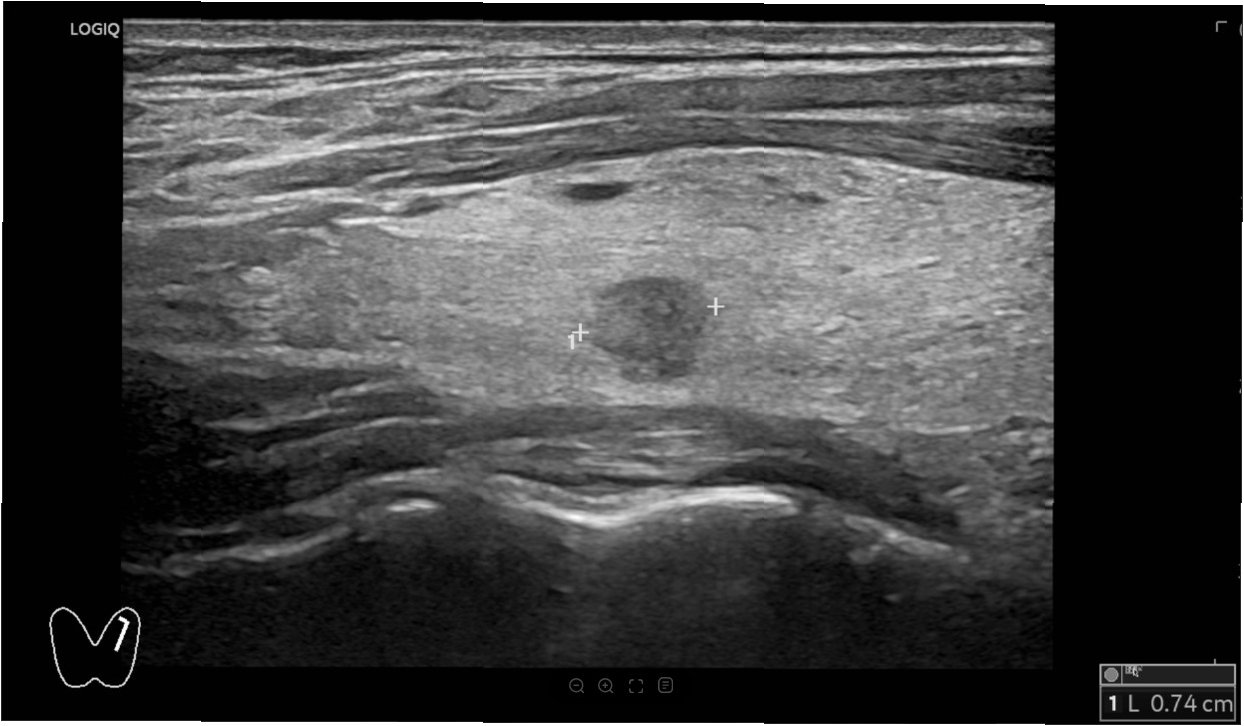

3. 갑상선 초음파 검사: 갑상선 결절의 모양, 크기, 내부 구조 등을 자세히 관찰하여 결절의 특성을 파악합니다.

4. 세침 흡인 검사 (FNA): 초음파를 보면서 가는 바늘로 결절의 세포를 채취하여 현미경으로 검사, 암 여부를 판단합니다.